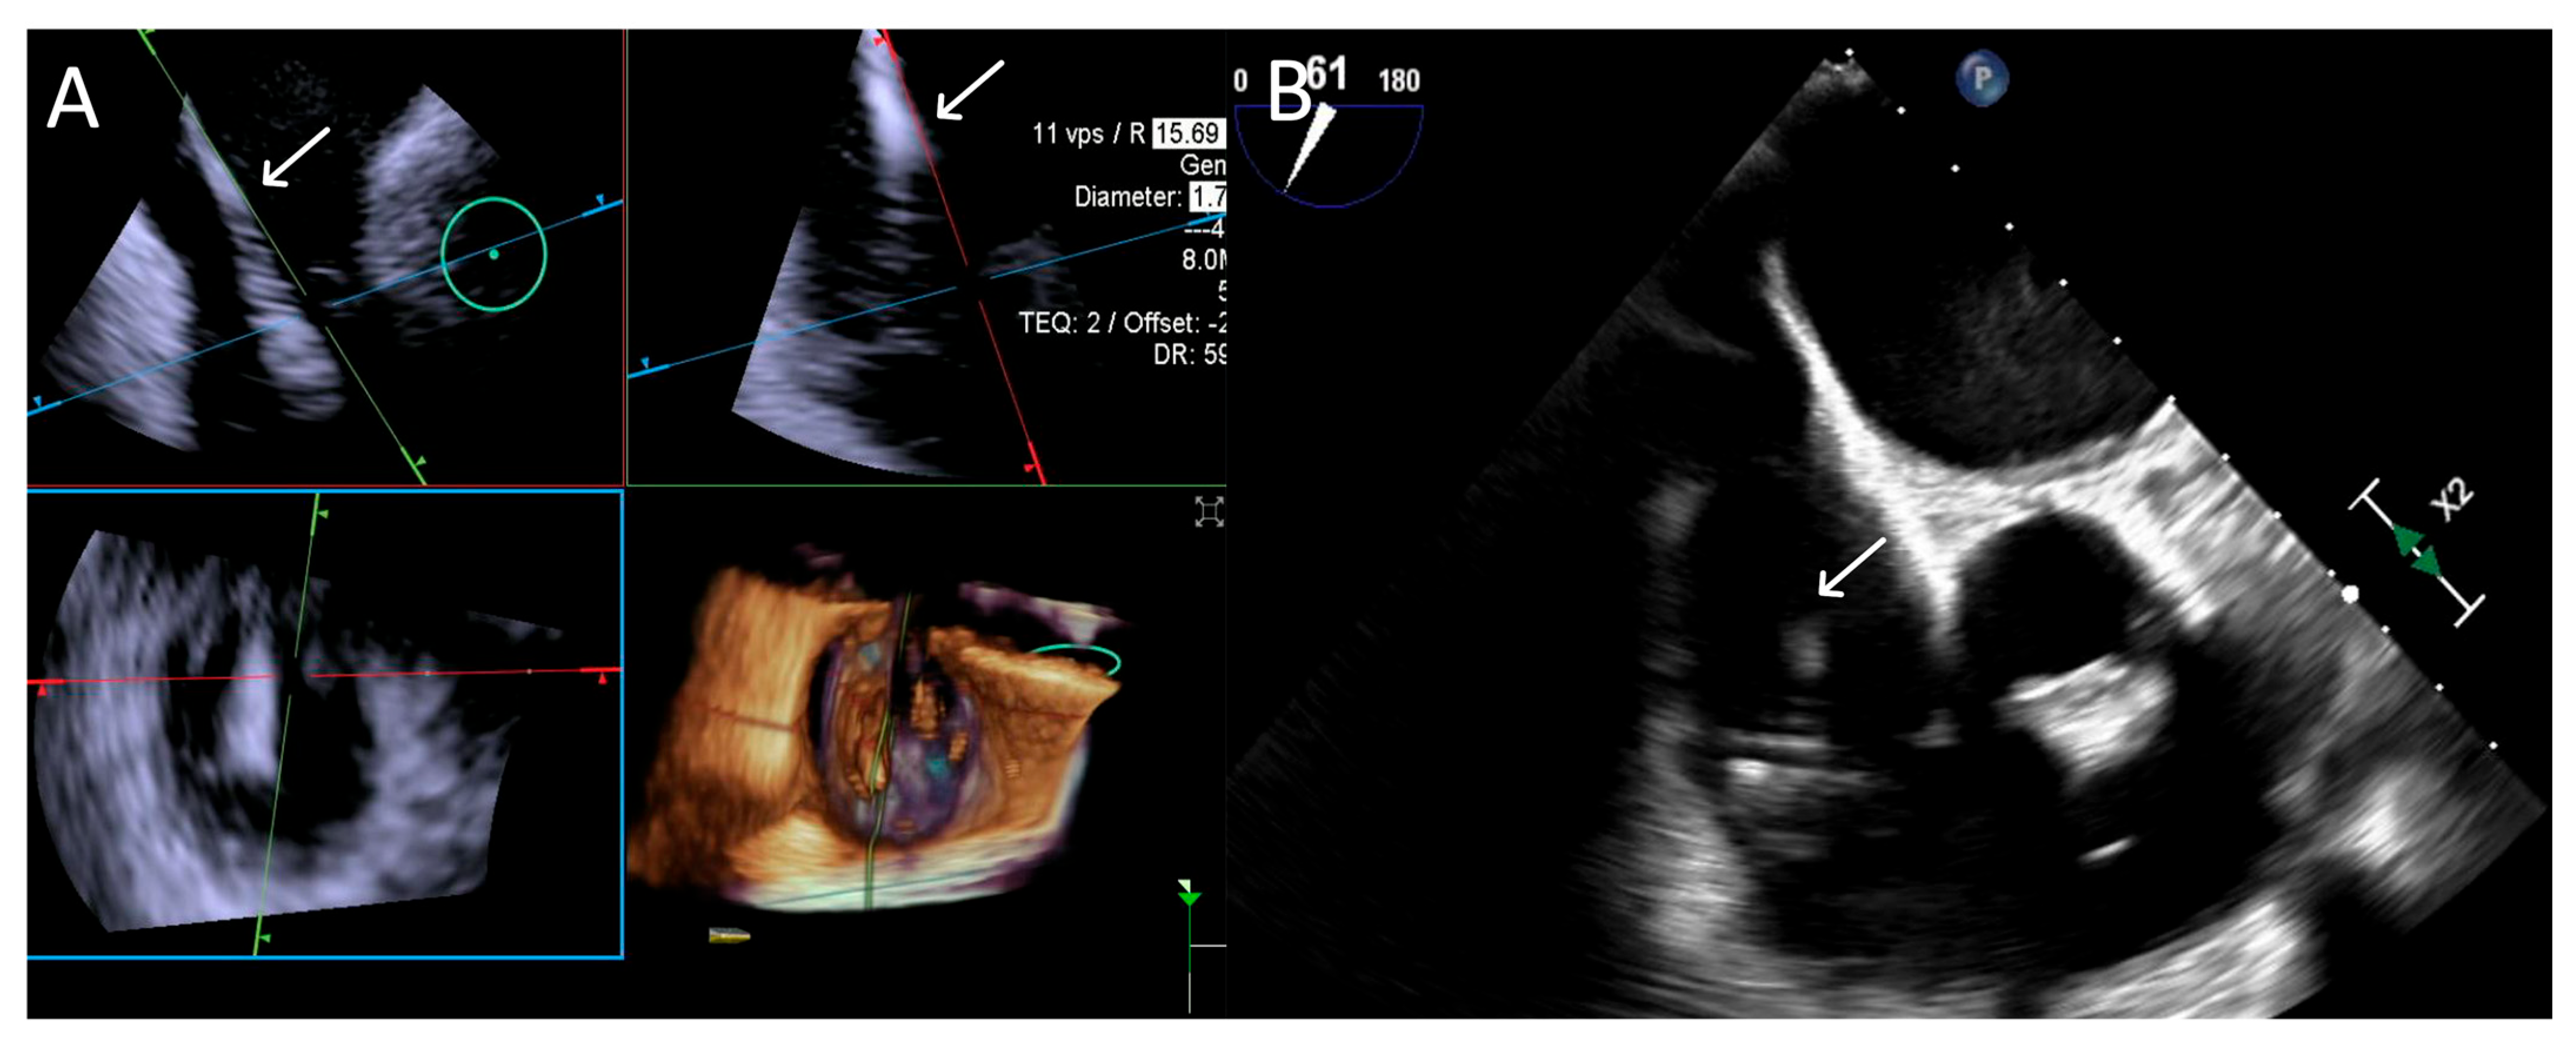

- Step number 7: leaflet insertion.

- Step number 8: evaluation of residual regurgitant jets.